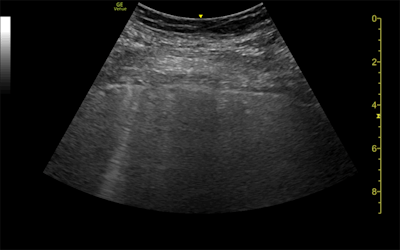

The three patients in the study, which was published in the Journal of Ultrasound in Medicine, had mild cases of COVID-19 but lingering shortness of breath. Ultrasound scans revealed a variety of pulmonary findings, including irregular pleural lines and B-lines, which correlated with abnormalities on CT scans.

- The 35-year-old woman had a mild, irregular pleural line and B-lines in her right anterior chest on ultrasound, which correlated with ground-glass opacities on CT.

- The 41-year-old woman had an irregular pleural line in her right lateral area on ultrasound, which correlated with pleural thickening on CT.

- The 64-year-old man had a marked, irregular pleural line and multiple B-lines on ultrasound, which correlated with fibrotic changes on CT.

Ultrasound could be one alternative for these patients because the modality is both affordable and radiation-free. The authors also pointed to ultrasound's widespread availability, quick exam time, and ease of use in both medical and nonmedical settings.

However, ultrasound has its own drawbacks, notably limited sensitivity. This was especially evident in the case of the 35-year-old woman whose mild irregular pleural line on ultrasound corresponded not to abnormal pleura on CT but parenchymal tissue changes.

"The findings in this report raise the question of whether lung ultrasound can be used in the longer-term follow-up of patients with COVID-19, by means of assessing still-symptomatic patients, as a radiation-sparing, novel care path worth exploring," the authors concluded.